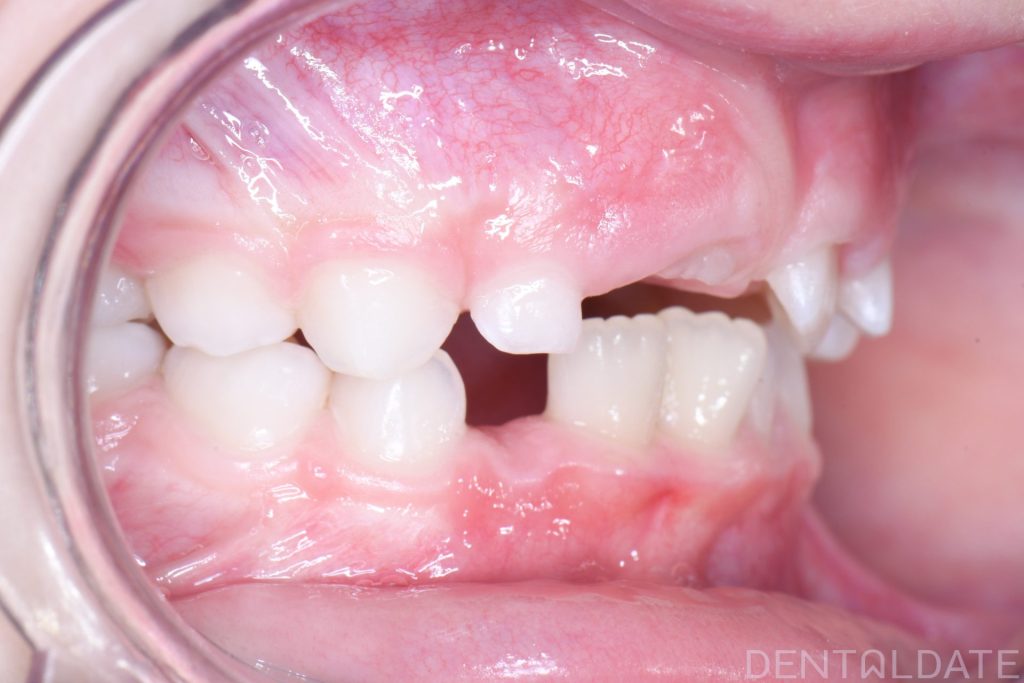

In this case, there was a severe lack of space for the permanent teeth, narrowing of the upper jaw, and the development of a malocclusion.